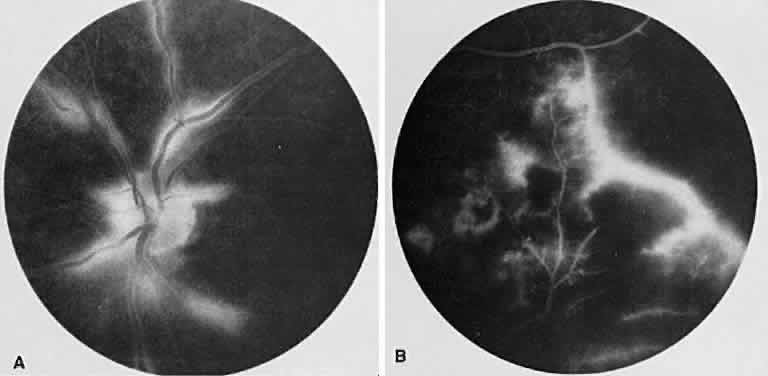

TUBERCULOSIS

Tuberculosis has numerous ocular presentations, including anterior uveitis, scleritis, sclerokeratitis, phlyctenulosis, interstitial keratitis, choroidal granulomas (often with serous elevations; Fig. 23A),retinal exudate, macular star formation, retinal vas-culitis, vitreous cells, SRNV, and optic nerve granulomas. Eales' disease, a bilateral peripheral vasculitis with peripheral neovascularization and vitreous hemorrhage, frequently occurs in young men who have positive purified protein derivative test results (Fig. 24).

Fig. 23. Tuberculoma. A. Subretinal tuberculoma. B. Multiple loculated areas of hyperfluorescence due to pooling of dye beneath the sensory retina.

Fig. 24. Eales' disease (retinal vasculitis). A. Angiography of the left disc shows staining of the retinal vessels, particularly the venules in the late venous stage. B. In the far periphery, there is staining of the peripheral vessels (particularly venules) just adjacent to an area of nonperfused retina. The hypofluorescent areas represent intraretinal hemorrhages.

On fluorescein angiography, a choroidal tuberculoma hyperfluoresces in the late phase (see Fig. 23B). There may be leakage and pooling of dye if there is a serous retinal detachment. As the tuberculoma responds to therapy, the hyperfluorescence decreases and pockets of hypofluorescence can be seen.79 Retinal arteriovenous shunts with dilated capillaries also can be seen in the granuloma.80 Peri-phlebitis causes capillary dropout and venous staining. Neovascularization of the peripheral retina is not uncommon.